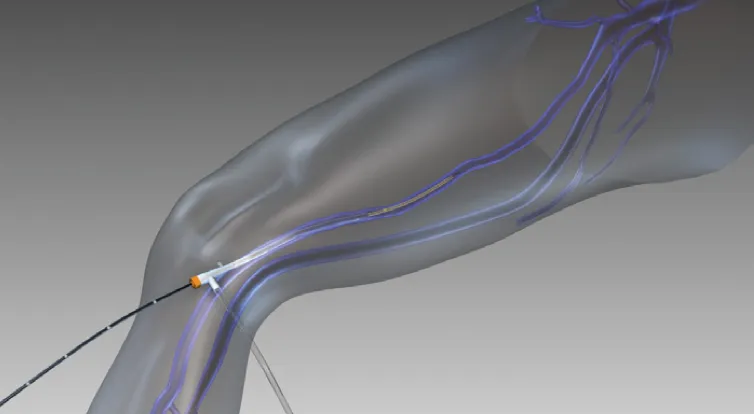

3. 静脉腔内热消融 (endovenous thermal ablation, EVTA)

国际上公认,伴有静脉曲张或静脉疾病症状或体征的N2静脉干功能不全的一线治疗是静脉内热消融(EVTA)。这通常通过静脉内激光消融(EVLA)或射频消融(RFA)进行,但也有其他形式的EVTA,如蒸汽静脉硬化(SVS)和静脉内微波消融(EMWA)

EVLA和RFA有多种不同的形式。在最基本的形式中,EVLA纤维可以是裸头的、套头的(减少静脉壁接触)、郁金香头的(防止所有静脉壁接触)或径向的(将激光能量侧向直接引导到静脉壁)——随着单环或双环径向纤维的出现。RFA装置可以是单极或双极的,通过电流通过静脉壁在射频频率引起加热,或部分,在装置的末端的金属线圈被射频电流加热,热量通过简单的传导进入静脉壁。